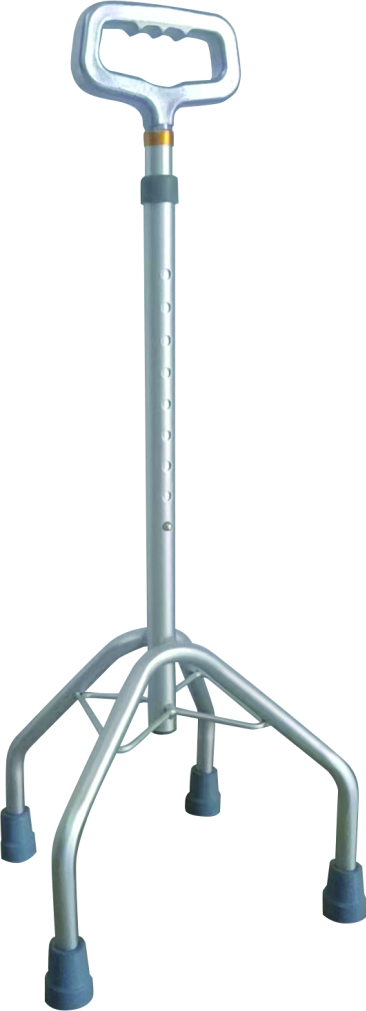

- Crutches

Crutches are an important medical rehabilitation AIDS, branch cane, elbow crutches, axillary crutches, multi-foot crutches, crutches play an important role in walking, not only to provide support and balance, but also to help improve gait and reduce energy consumption